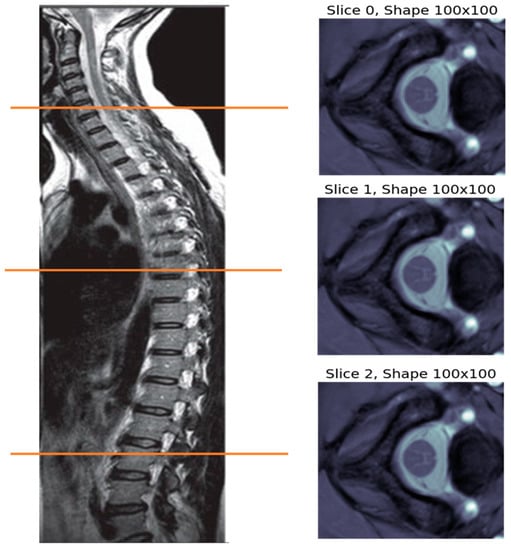

The MR image captured from each subject is a 3D volume with size R × C × S, which stands for rows, columns, and slices, respectively. Figure 1 shows the MRI volume captured for subject 1 of site 1, which is composed of three slices. These slices represent views at certain cut locations from the spinal cord, as indicated by the colored horizontal lines on the left part of the figure.

Figure 1. MRI volume for subject 1 of site 1, which is made up of three MRI slices captured at certain locations in the subject’s spine, as indicated by the colored horizontal lines.